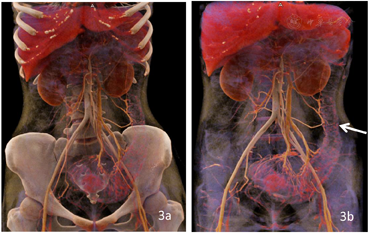

CT图像显示结肠肠壁弥漫性均匀增厚,最厚处约1.5cm,病变肠管内壁呈凹凸不平锯齿样改变,增强扫描呈明显分层强化,病变肠管管腔变细,系膜侧小血管增多、增粗、迂曲。患者随后进行了肠镜和病理活检,病理结果显示为溃疡性结肠炎。临床诊断为慢性复发型全结肠型重度溃疡性结肠炎活动期。给予对症治疗和美沙拉嗪抑制免疫治疗,病情好转。

UC是一种非特异性慢性炎症性肠病,病因不明,易复发。诊断主要基于临床症状、实验室结果、内镜及组织学评估[1]。由于内镜是侵入性检查,部分患者无法忍受,且内镜检查无法观察肠外情况[2]。且对于不同分级、分期、病变部位的患者采用不同的治疗方法,准确诊断疾病对治疗及预后至关重要[3]。CTE可作为内镜检查的辅助检查手段,用于评估病变范围、分布、严重程度、病情分期、肠外情况及并发症[4]。CTE是采用双能量进行扫描,检查前患者饮用大量水,将肠腔充盈,有利于显示肠壁及腔内情况,在140kV下采集的CT图像较80KeV对比度增强,两者的融合图像对病变显示最佳(图1,图2)。同样的数据可用于进行MIP和CR后处理,不增加患者的辐射剂量,在MIP图像上,能够显示病变肠管周围的肠系膜血管,对"齿梳征"的显示更加清楚;在CR图像上能显示UC特有的"舞龙征"[5],有助于UC的诊断。骨结构可以通过syngo.CT Direct Angio去除,以清晰显示血管和病变肠管(图4b)。所有这些应用程序都是在自动化的工作流中执行的。